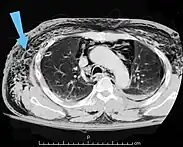

Significant cases of subcutaneous emphysema are easy to diagnose because of the characteristic signs of the condition.[1] In some cases, the signs are subtle, making diagnosis more difficult.[13] Medical imaging is used to diagnose the condition or confirm a diagnosis made using clinical signs. On a chest radiograph, subcutaneous emphysema may be seen as radiolucent striations in the pattern expected from the pectoralis major muscle group. Air in the subcutaneous tissues may interfere with radiography of the chest, potentially obscuring serious conditions such as pneumothorax.[18] It can also reduce the effectiveness of chest ultrasound.[27] On the other hand, since subcutaneous emphysema may become apparent in chest X-rays before a pneumothorax does, its presence may be used to infer that of the latter injury.[13] Subcutaneous emphysema can also be seen in CT scans, with the air pockets appearing as dark areas. CT scanning is so sensitive that it commonly makes it possible to find the exact spot from which air is entering the soft tissues.[13] In 1944, M.T. Macklin and C.C. Macklin published further insights into the pathophysiology of spontaneous Macklin's Syndrome occurring as a result of a severe asthmatic attack.